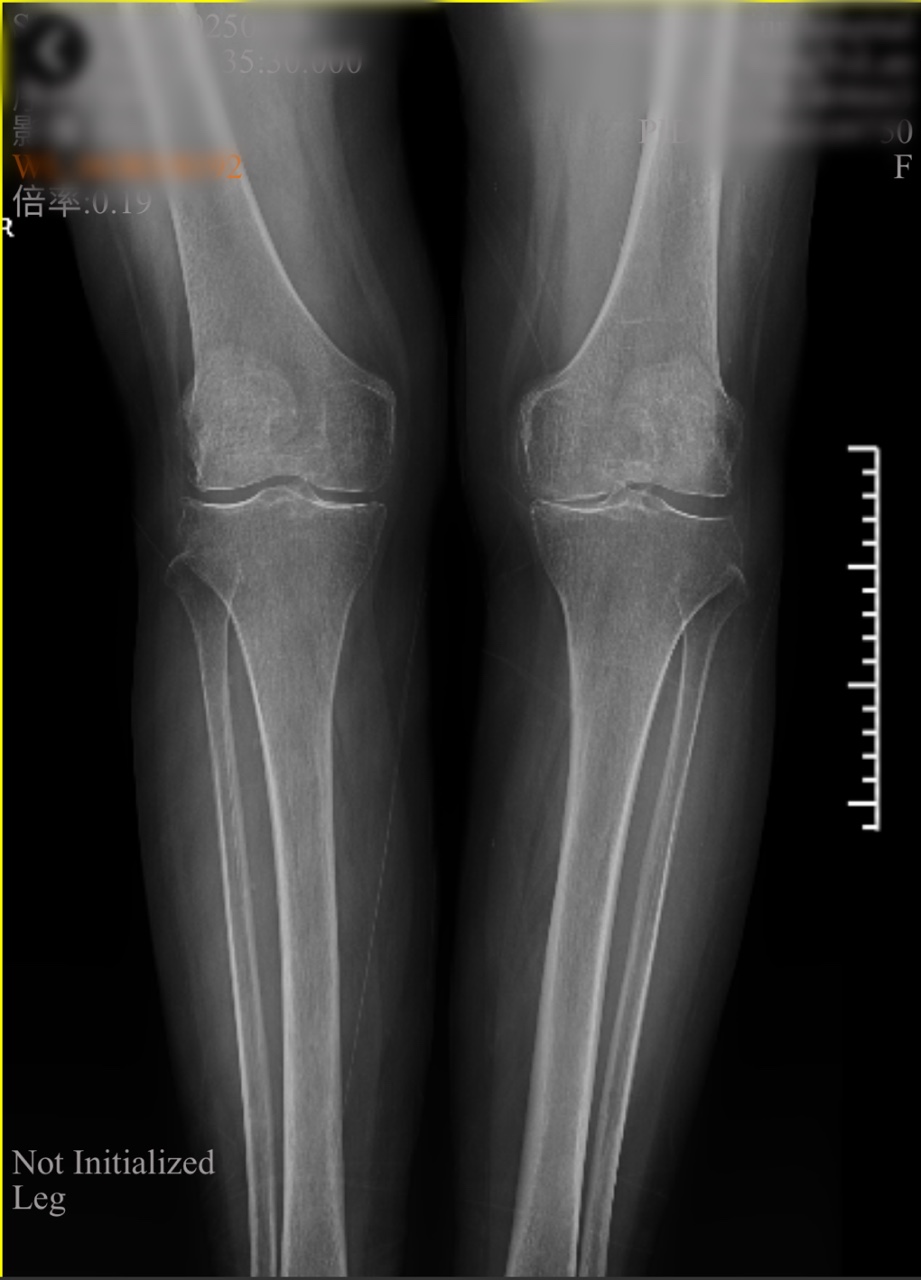

檢查室里,魏海清主任帶領(lǐng)團(tuán)隊(duì)為李阿姨做了詳細(xì)查體。“膝蓋內(nèi)翻畸形,軟骨剝脫,關(guān)節(jié)間隙明顯變窄......”影像學(xué)檢查證實(shí)了醫(yī)生的判斷:左膝關(guān)節(jié)骨質(zhì)增生嚴(yán)重,關(guān)節(jié)面硬化,屈伸活動(dòng)已嚴(yán)重受限。

傳統(tǒng)的全膝關(guān)節(jié)置換固然能解決問題,但創(chuàng)傷較大、恢復(fù)期長。經(jīng)過團(tuán)隊(duì)綜合評估,魏海清主任提出了一個(gè)更精細(xì)的方案:“我們建議行左膝關(guān)節(jié)單髁置換術(shù)。這就像牙齒壞了,我們不必把所有牙齒都換掉,而是只替換損壞的部分。這種手術(shù)只替換磨損的軟骨和部分骨質(zhì),能最大限度保留健康組織。”他拿出膝關(guān)節(jié)模型,耐心地向一家人解釋手術(shù)原理:“您看,膝關(guān)節(jié)分為內(nèi)側(cè)、外側(cè)和髕股三個(gè)部分。您的磨損主要集中在內(nèi)側(cè),所以我們只需置換這一部分。”這種個(gè)體化、精準(zhǔn)化的治療理念,讓原本忐忑的一家人逐漸安心。